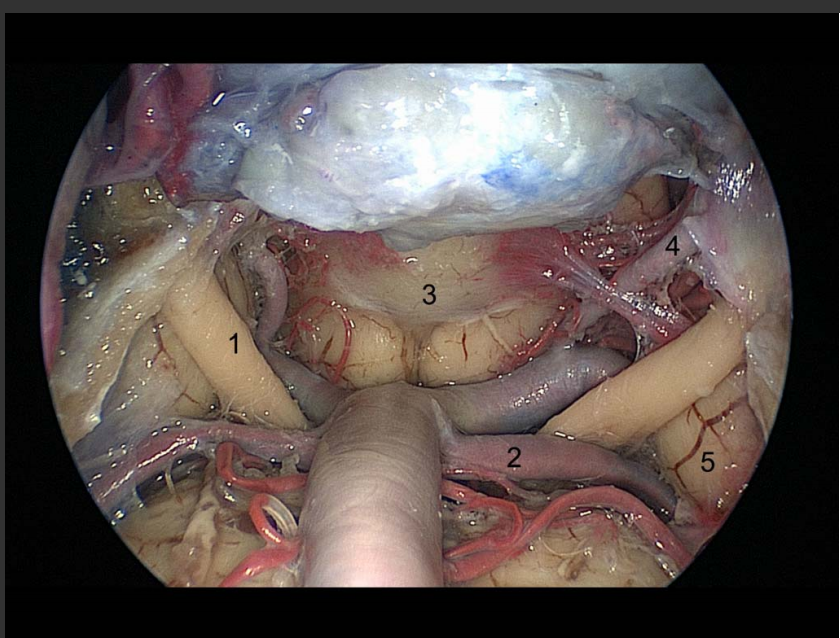

The following figure depicts an endoscopic view of the upper clival/retrosellar region in a cadaveric dissection. Which cranial nerve is indicated by numeral 1.

E. Abducens I

A

B. Oculomotor